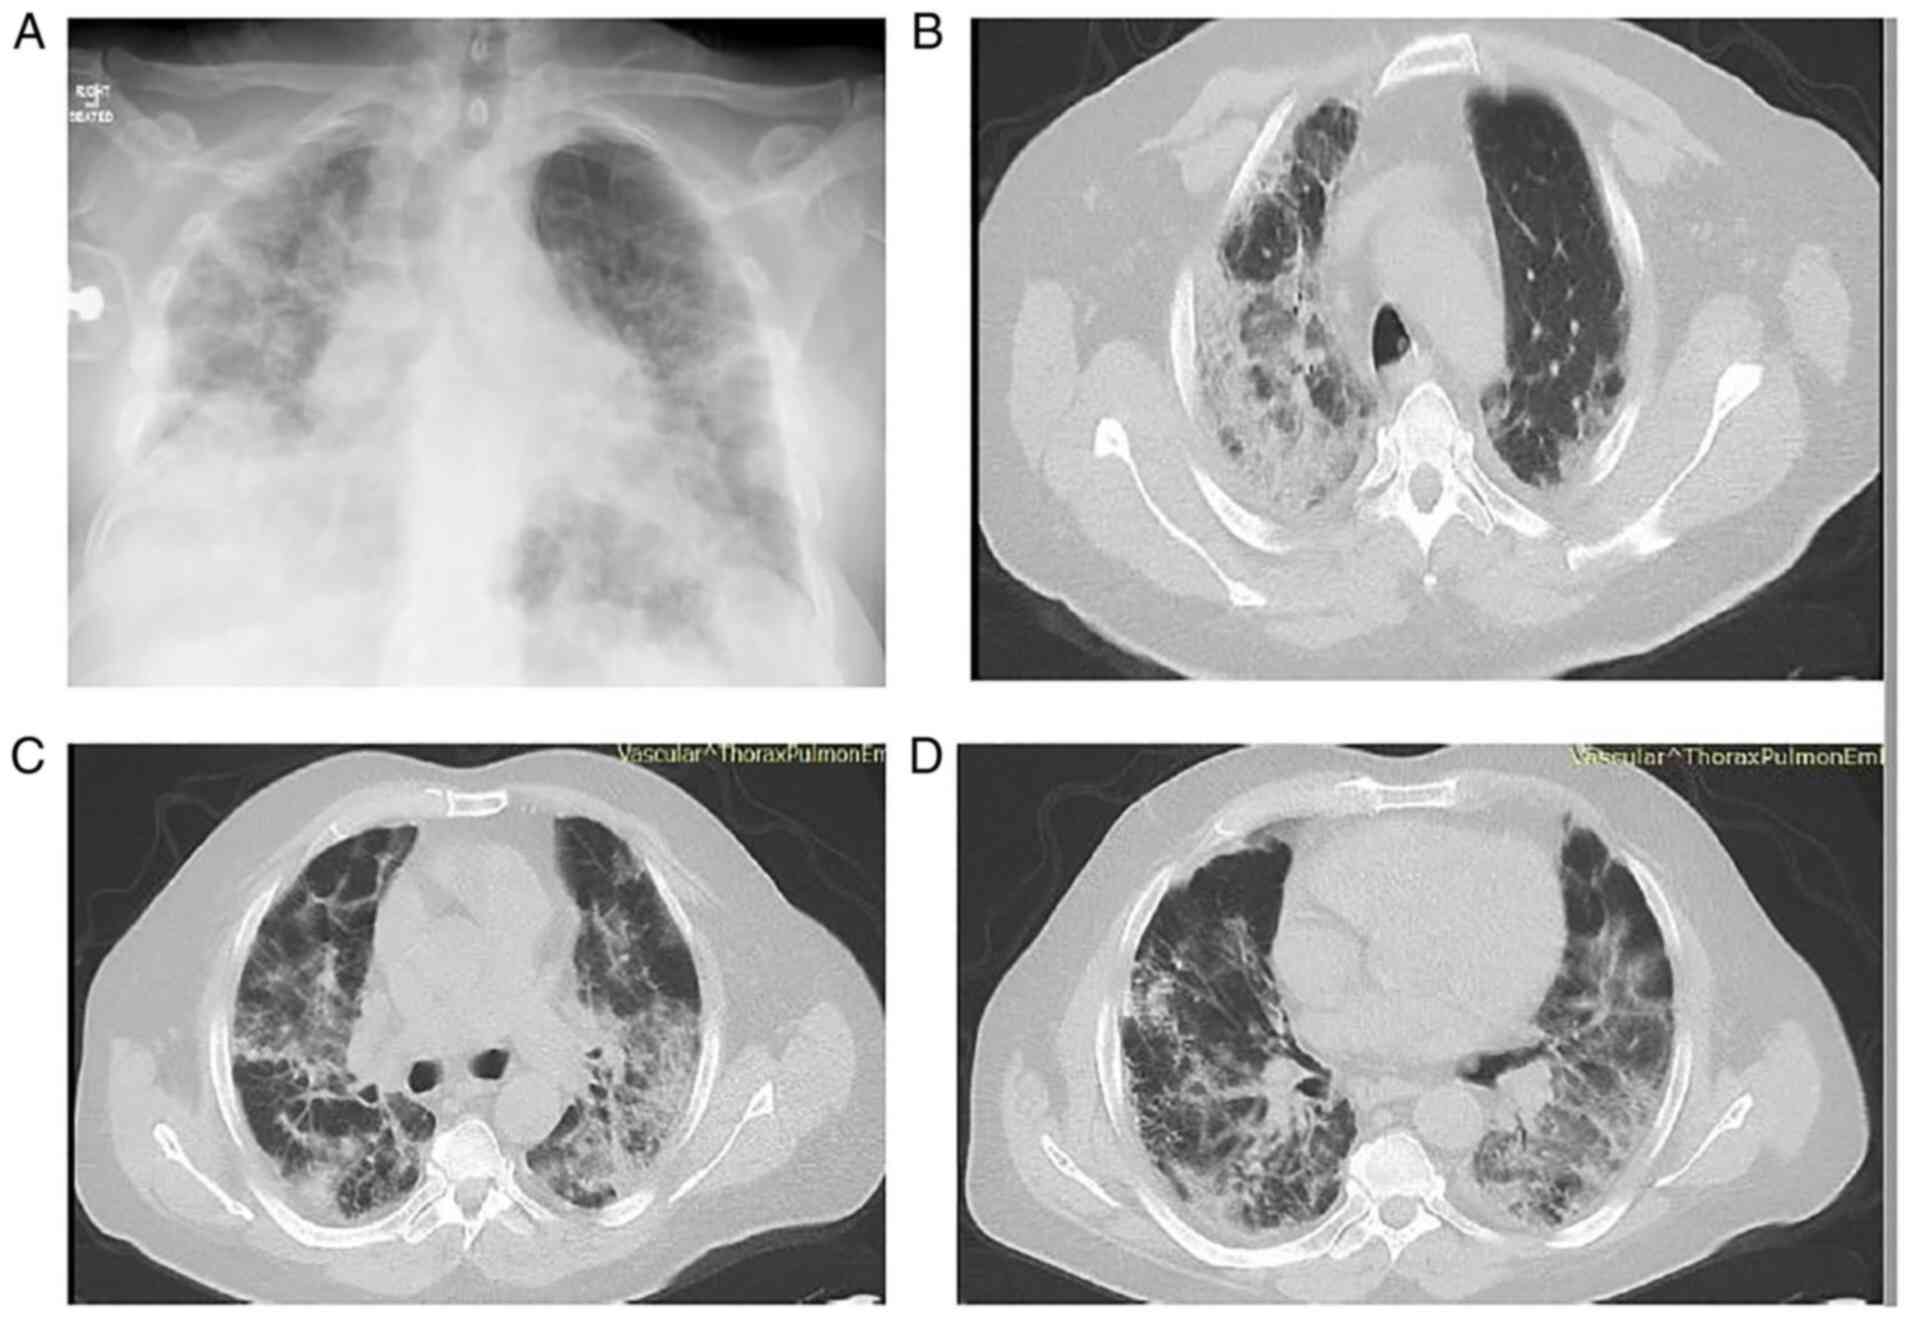

The patient underwent a new chest X-ray, which revealed persistent infiltrates in all lung fields with consolidations in the right upper and middle lung field, and in the left middle lung field (Fig. 5A). He also underwent a chest CT scan and CTPA, which revealed bilateral consolidations with areas of reversed halo sign in all lung fields and peripheral GGO infiltrates in both lower lung lobes (Fig. 5B-D). There were no findings suggesting pulmonary embolism. No infectious microorganisms were isolated from blood and sputum cultures. Based on the clinical and radiological data, COVID-19-associated OP was suspected, and systemic corticosteroid therapy (methylprednisolone at 1 mg/kg/day) was initiated on day 15 (day 28 of illness). On day 18, at 3 days following the commencement of corticosteroid therapy (day 31 of illness), his oxygenation level improved considerably. A chest X-ray and CT imaging performed on day 13 following the commencement of corticosteroid therapy (day 28 of hospitalization, day 41 of illness) revealed a notable improvement in previously noted lung infiltrates (Fig. 6). The levels of CRP also returned to normal. Methylprednisolone administration was decreased to 40 mg, and the patient was discharged on day 33 after admission (day 46 of illness). Following discharge, methylprednisolone administration was decreased to 32 mg for 7 days, 16 mg for 7 days and 8 mg for 7 days, and discontinued thereafter. The patient did not present with a relapse and he had improvement in chest X-ray at a follow-up 2 months after discharge (Fig. 7).

Figure 5

Chest X-ray and computed tomography of the patient in case 2 on day 13 of hospitalization. (A) Chest X-ray illustrating persistent infiltrates in all lung fields with consolidations in the right upper and middle lung field and in the left middle lung field. (B and C) Chest computed tomography illustrating bilateral consolidations with areas of reverse halo sign in upper lung fields. (D) Chest computed tomography illustrating bilateral consolidations with areas of reverse halo sign and peripheral ground glass infiltrates in both lower lung lobes.

Figure 6

Chest X-ray and computed tomography of the patient in case 2 performed on day 13 following the commencement of corticosteroid therapy. (A) Chest X-ray illustrating an improvement in lung infiltrates compared to Fig. 5A. (B and C) Chest computed tomography illustrating an improvement in lung infiltrates in upper lung fields. (D) Chest computed tomography reveals improvement in lung infiltrates in both lower lung lobes.